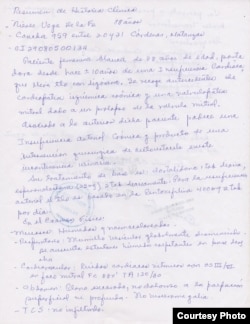

Vega de la Fe tiene edemas en los pies y padece una cardiopatía, “y se deteriora en estas circunstancias”, subrayó Alfonso Vega, quien alertó que su madre también "tiene una sepsis en los ojos, que tengo de hecho que llevarla al oculista”.